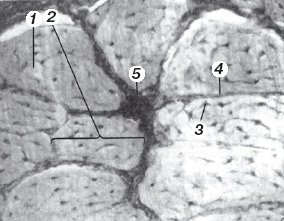

Сухожилия состоят из толстых, плотно лежащих параллельных пучков коллагеновых волокон. Между этими пучками располагается тонкая эластическая сеть, а также имеются небольшие пространства, заполненные основным веществом. Из клеточных форм в сухожилии имеются только фибробласты, которые располагаются параллельными рядами в пространствах между пучками волокон. На поперечных срезах можно видеть, что тонкие пластинчатые отростки фибробластов со всех сторон окружают пучки волокон и тесно соприкасаются друг с другом. Фибробласты сухожильных пучков часто носят специальное название сухожильных клеток (рис. 1).

Рис. 1. Поперечный срез сухожилия:

1 - пучок коллагеновых волокон первого порядка;

2 - пучок второго порядка;

3 - сухожильные клетки;

4 - эндотенон;

5 - перитенон.